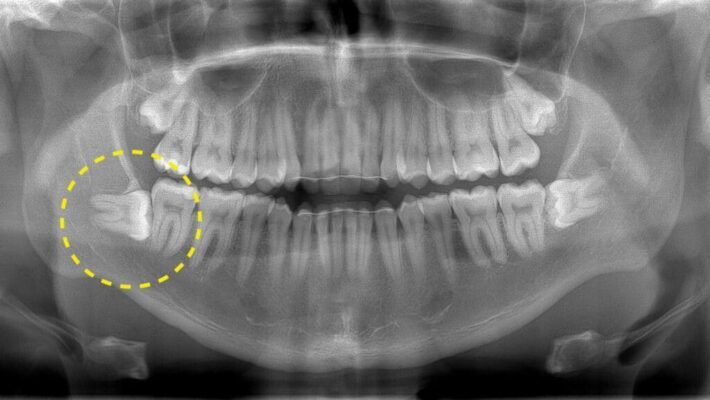

- Не вистачає місця: Можливо, ваша щелепа буквально занадто мала.

- Кривий ріст: Навіть найбільш дисципліновані зуби можуть розвинути свій “вибагливий” характер.